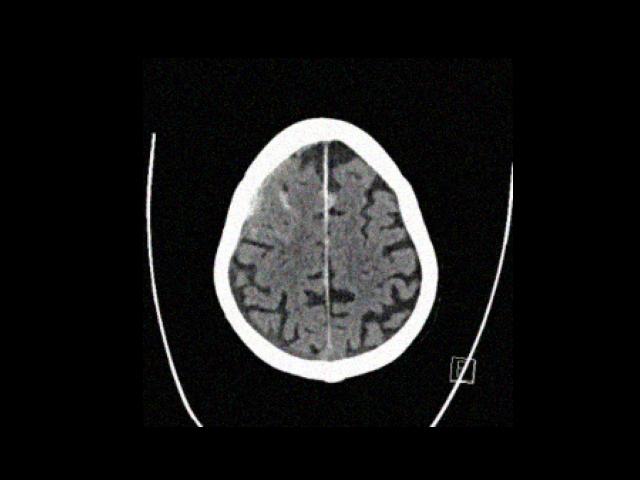

Sample Gallery